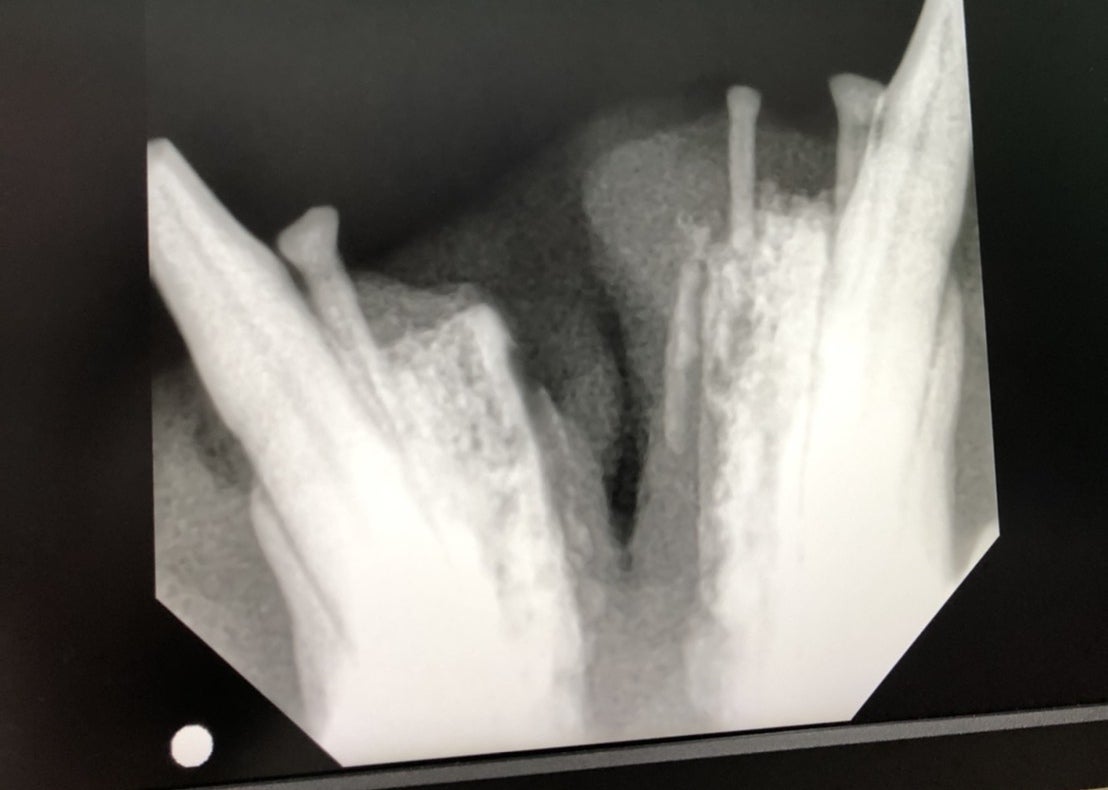

見つけた時の姿はとても酷く、傷口が化膿して顔は膿だらけで鼻からも夥しいほどの膿が流れ出ていました。

保護猫改めニャン吉は必死に生きています。病院の先生にもよく生きていたね、と驚かれた程です。